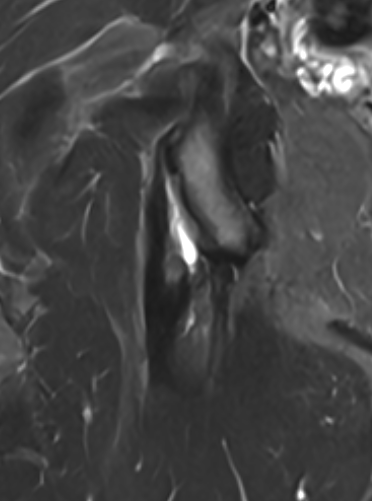

High grade partial tear proximal hamstring